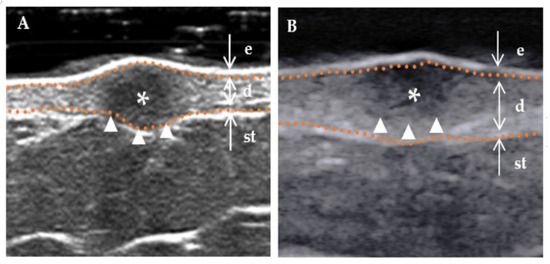

Figure 3.

The internal echogenicity of DF lesions. * Indicates the precise location of the lesion on the ultrasound image. The skin layers are indicated by dotted orange lines, with arrows indicating a hyperechoic epidermis (e), an isoechoic dermis (d), and a subcutaneous tissue (st). (A) The internal echogenicity of the mass is homogeneously distributed: the mass exhibits a homogeneous low echogenicity pattern with similar echogenicity distribution in any direction. (B) The internal echogenicity of the mass is heterogeneously distributed: the core of the mass is hypoechoic compared to the cortex (cortical portion), which is more echogenic.